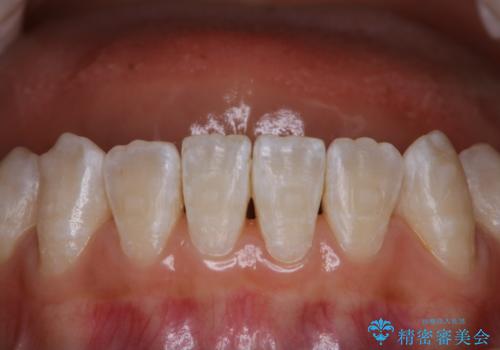

- マスクの着用により、以前より口臭が気になるとのことでした。しっかりと全体的なクリーニングを希望されたため、PMTC60分コースを行いました。

PMTCとはProfessinnal Mechanical Tooth Cleaning・専門器具による歯の機械的な清掃です。

バイオフィルム(細菌の塊)を破壊し、歯の表面をツルツルにすることでお口の中の細菌数を減らし歯周病のリスクが定着するのを防ぎます。更に、歯に新しい汚れがつきにくい状態になります。

バイオフィルムが除去されると、ご自身本来の歯の表面になります。PMTCをすることで口臭予防にもなり、定期的に行うことが大切です。